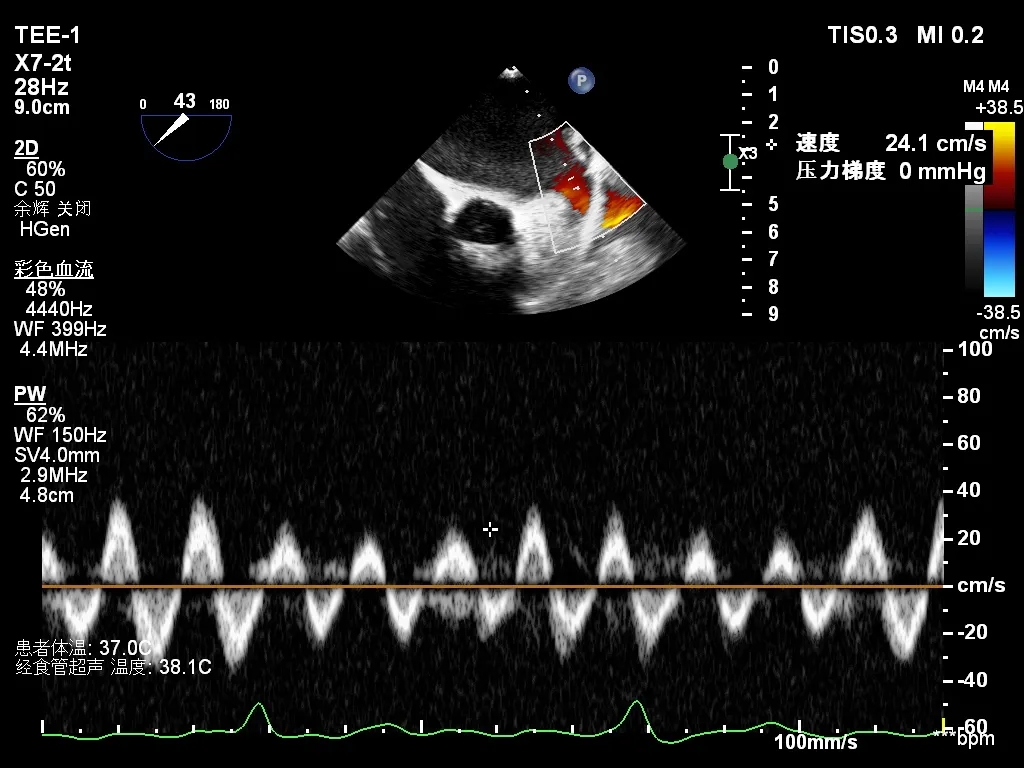

常规经食道超声心动图(TEE)评估发现,左心耳血流速度明显减慢,流速约 24 cm/s,提示存在血栓形成高风险因素,但左心耳内未见自发显影。此外,TEE发现巨大房间隔膨胀瘤(ASA,大小约28×10mm),同时合并卵圆孔未闭(PFO),且ASA腔内可见明显自发性显影(SEC),其内血流速率明显减慢(20.8cm/s)。

左心耳排空速度测量